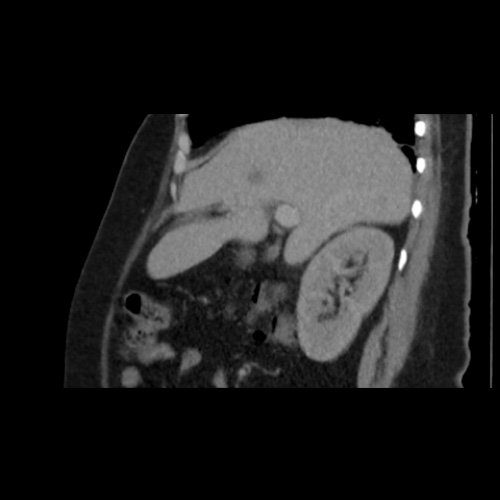

TC de abdomen y pelvis con contraste endovenoso (12/02/2026) Corte coronal: hígado de forma, tamaño y situación habituales, con superficie lisa y bordes agudos.  Imagen hipovascular aislada de 15 mm en segmento V de aspecto inespecífico.

TC de abdomen y pelvis con contraste endovenoso (12/02/2026) Corte sagital: hígado de forma, tamaño y situación habituales, con superficie lisa y bordes agudos.  Imagen hipovascular aislada de 15 mm en segmento V de aspecto inespecífico.

• Tomografía de abdomen y pelvis sin contraste oral con contraste EV (12/02/26):  El hígado es de forma, tamaño y situación habituales. Su superficie es lisa, y sus bordes son agudos. Imagen hipovascular aislada de 15 mm en segmento V de aspecto inespecífico. Sugiero complementar con RMI. La vía biliar intra y extrahepática es de calibre conservado. La vesícula biliar es de forma, tamaño y situación normales, sin imágenes que sugieran la presencia de litiasis. Tener en cuenta que este método puede pasar por alto litiasis colesterínicas. El bazo es de forma, tamaño y situación normales. El páncreas es de características normales. El conducto de Wirsung es de calibre conservado. Adenoma adrenal izquierdo de 16 mm. Ambos riñones son de forma, tamaño y situación habituales. Concentran y eliminan adecuadamente la sustancia de contraste. Sin evidencia de alteraciones calicopiélicas ni ureterales. La aorta, las arterias ilíacas primitivas, internas, externas y femorales, son de calibre y trayecto conservado, permeables. La vena cava inferior y las venas ilíacas primitivas, internas, externas y femorales son de calibre y trayectoria conservados, permeables. No se observan adenomegalias intraperitoneales, retroperitoneales, ilíacas ni inguinales. No se observan alteraciones a nivel del tracto gastrointestinal. La vejiga es de paredes lisas, sin presentar efectos de masa endoluminales ni parietales. Utero en AVF, lateralizado a izquierda. Pequeña hernia umbilical de contenido graso y escaso líquido intrasacro. No se identifican alteraciones en las estructuras óseas visualizadas.